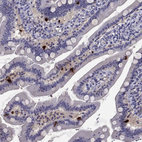

Immunohistochemistry analysis in human duodenum and skeletal muscle tissues using HPA069515 antibody. Corresponding CCK RNA-seq data are presented for the same tissues.